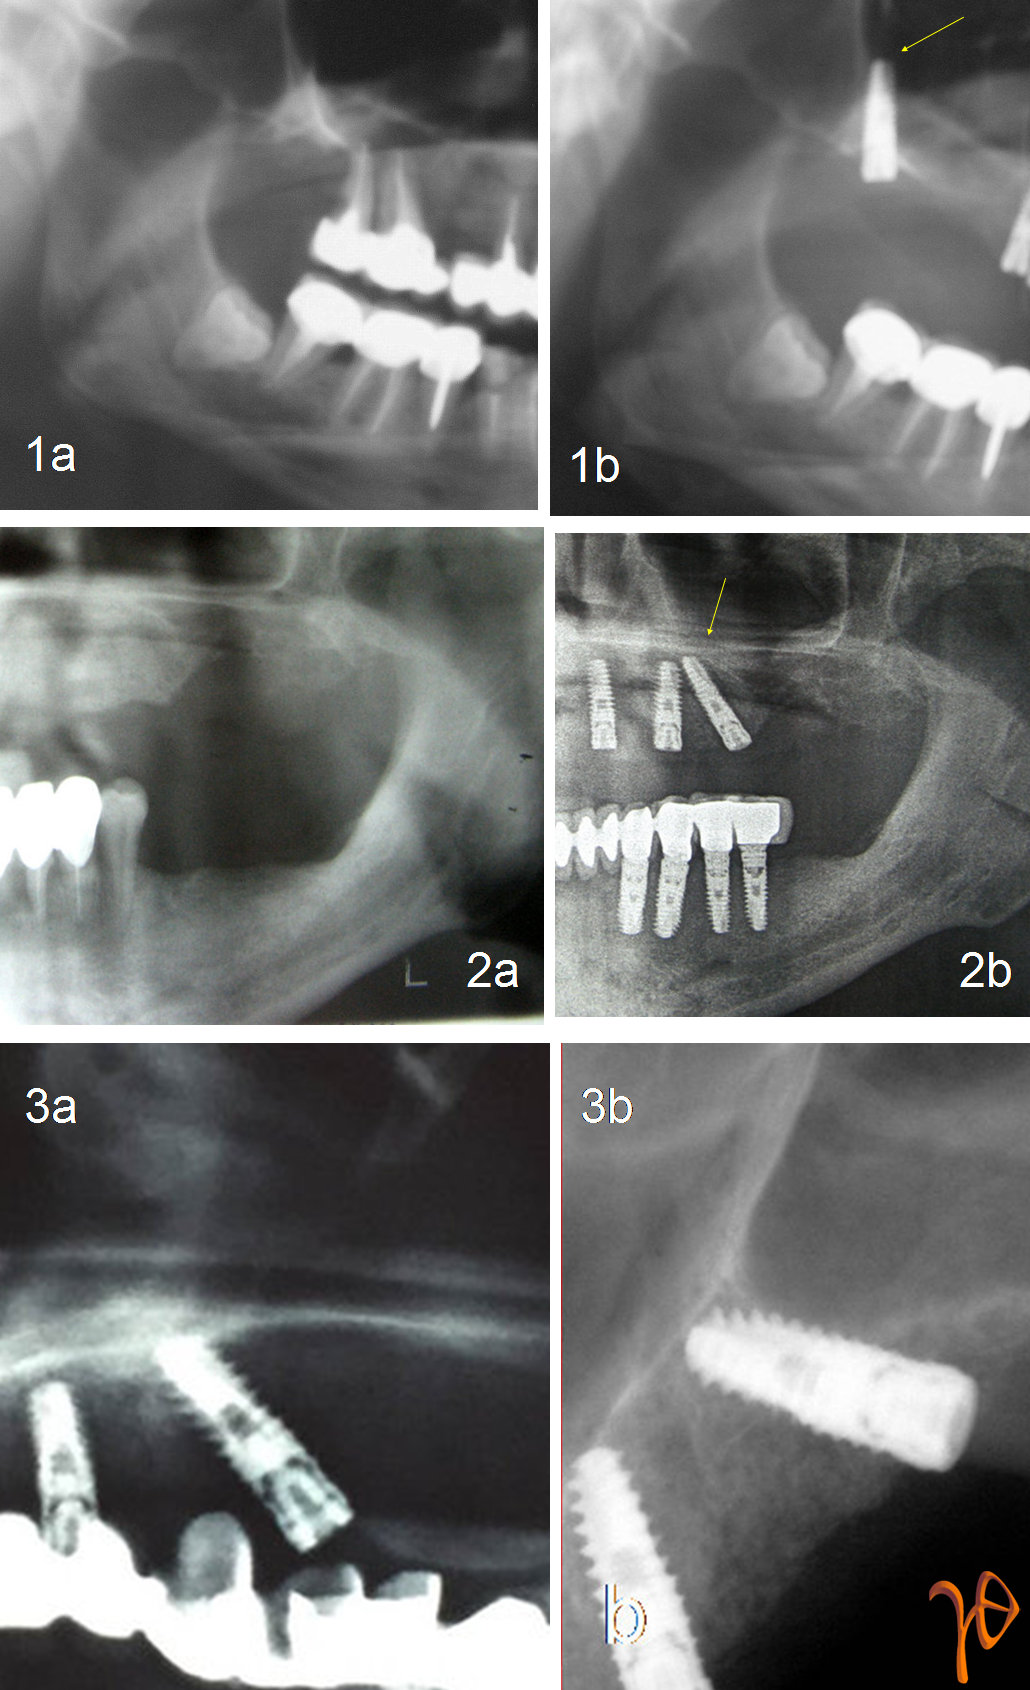

Με αυτό τον τρόπο τεχνικές, όπως η all-in-four στην κάτω γνάθο, μπορεί να πραγματοποιηθεί με ασφάλεια χωρίς διεγχειρητική αναγνώριση του γενειακού νεύρου, και η παράκαμψη του ιγμορείου μπορεί να μην βασίζεται απλά στην εμπειρία του επεμβαίνοντος όταν τοποθετούνται εμφυτεύματα με κατεύθυνση προς τη ρινογναθική αντηρίδα ή το γναθιαίο κύρτωμα, με μικρότερη ή μεγαλύτερη επιτυχία(Εικόνα 1).

Εικόνα 1. Περιπτώσεις εμφυτευμάτων υπό γωνία χωρίς την βοήθεια υπολογιστή. Κρίνοντας από την περίπτωση #3, όπου η πανοραμική απεικονίζει "εσφαλμένα" το εμφύτευμα μέσα στο ιγμόρειο, θα μπορούσαμε να ισχυριστούμε ότι το ίδιο ισχύει για την περίπτωση#1. Ωστόσο το "τυφλό" της τεχνικής παραμένει.